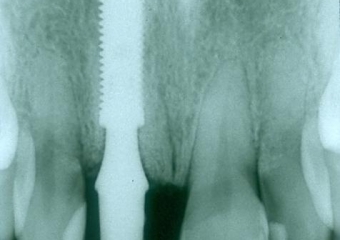

Raio X da prótese provisória

Prótese provisória fixa sobre implante cone Morse